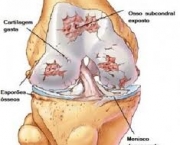

O desenvolvimento dessa doença se dá pelo desgaste das cartilagens responsáveis por revestir as extremidades ósseas de forma a causar muita dor e até mesmo deformações. A incidência de Artrose no Joelho é bastante comum porque as articulações do joelho estão dentre as articulações mais afetadas pela sobrecarga de peso.

Outro sintoma bastante significativo desse problema nos joelhos é sentir um tipo de crepitação quando faz algum movimento com os joelhos. Devido ao crescimento de ossos ao redor do joelho o indivíduo sente que o joelho está inchado. Quando uma pessoa começa a sentir além de dores nos joelhos perda de sua função (de aguentar carga) deve procurar por um especialista.